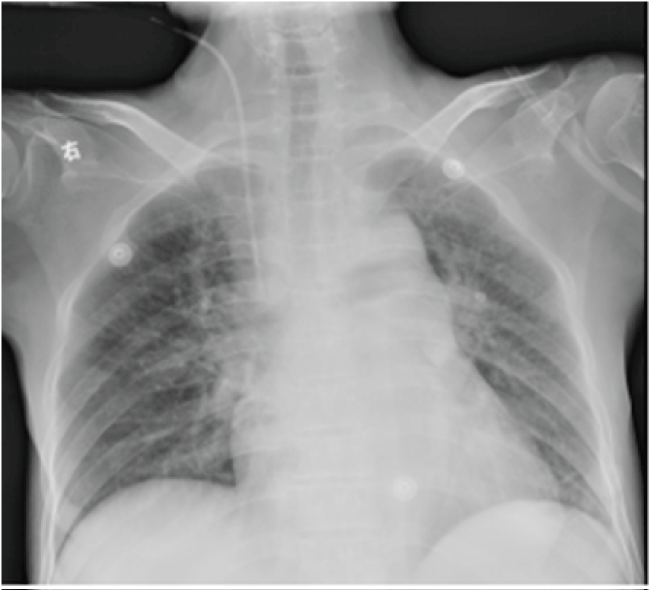

Figure1 1: The same post-operative day X-ray confirmed the safe positioning of central venous catheter.

At the first post-operative day, she complained of mild pain at incision site. The patient have a same day post central venous catheterization X-ray with normal chest radiography (Figure 1). On the morning of postoperative day 2, she was in respiratory distress with tachypnoea, mucosa cyanosis and began to report chest pain during the inspiration phase. The extremities were clammy. Arterial blood gas showed severe hypoxia, with sudden fallen of arterial oxygen pressure (PaO2 123 mmHg to 31 mmHg). A suspicion of pulmonary embolism or acute heart failure raised. N-terminal Pro-Brain Natriuretic Peptide and cardiac troponin I were immediately determined but without elevation. An emergent lung spiral computed tomography (CT) scan was performed. No thrombus was obtained but an unexpected malposition of the catheter tip that was complicated with severe bilateral pleural effusion and mild pneumomediastinum (Figure 2). By tracking the position of catheter from IJV till subclavian vein, catheter was found intravascularly located at the entire route of IJV (Figure 2A and Figure 2B) and segment of subclavian vein (Figure 2C and Figure 2D). However, the catheter tip did not proceed to superior vena cava as expected, but distorted and bent forward, and rotated leftward as depicted by the images taken from three-dimensional CT (Figure 3), which clearly illustrated the entire journey of the CVC. During the stay in intensive care unit, intermittent thoracentesis and chest drainage, along with continuous oxygen therapy, analgesia, were immediately implemented. The catheter was gently removed under ultrasound guidance. The vital parameters were monitored. Care was taken to prevent vascular rupture and detachment of thrombosis. All the drainage tubes were removed and the patient was safely transferred to the wards at postoperative day 7.

This is the first experience of late migration of right IJV catheter in our department. Bending of the catheter is very rare because the right internal jugular vein is the straight route for catheterization to the right atrium. In the present case, the initial position of the catheter is corrected located, which was confirmed by the catheter that was functioning well with blood aspiration and as a canule for anesthetics infusion. Drug effect was obtained intraoperative through administration of sedation/analgesia through this catheter. Central venous pressure monitoring showed no other abnormal findings. The chest X-ray at the same day of post central venous catheterization confirmed the safe positioning of the catheter, but the images reveals that the catheter is inserted very proximal to the mediastinal structures through the jugular (Figure 1), that makes the peri-IJV structure vulnerable to mechanic injuries.